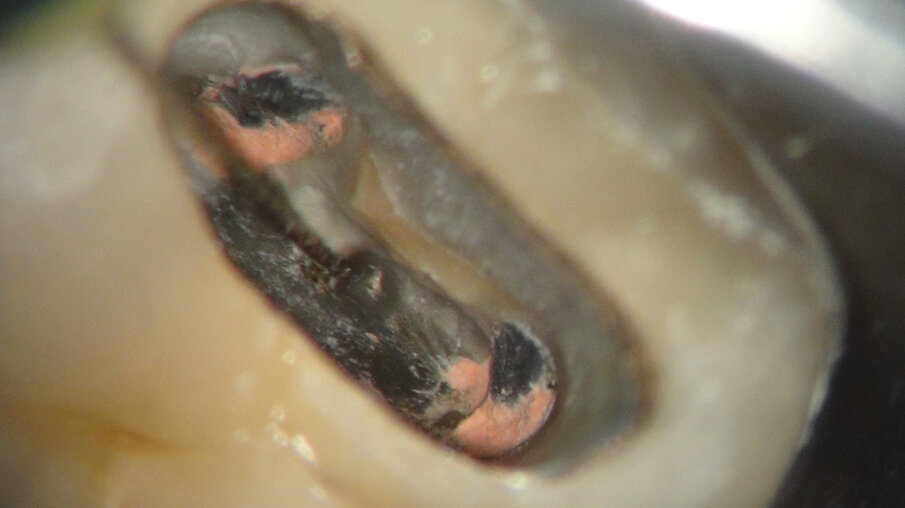

Na anesthesie en rubberdam maken we de access (afbeelding 8 en 9). De zwarte plastic Thermafil carriers zijn duidelijk te zien. Na wat gutta verwijderd te hebben, blijft er op de isthmus iets guttapercha achter. Zou ik dan toch vier jaar geleden een MidMesial gemist hebben (afbeelding 10)? We richten onze inspanningen eerst op de midmesial. Een uur later geef ik het op. Ik durf ook niet verder af te dalen in het relatief smalste deel van de mesiale radix. Het gevaar op een perforatie wordt me te groot (afbeelding 11 en 12).

Afbeelding 10. Het is mogelijk dat we 4 jaar geleden een MidMesial gemist hebben.

Afbeelding 11. Het gevaar op een perforatie wordt te groot.